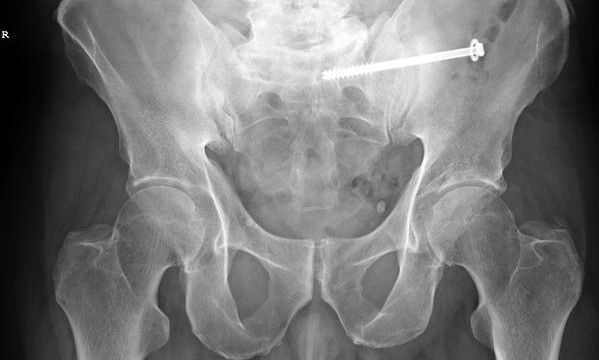

The company Synthes Costa Rica S.C.R. Ltda provides elastic titanium nails and osteosynthesis systems to 24 hospitals in this Central American country through a contract with the Caja Costarricense de Seguro Social (CCSS). The company’s current contract will finish in September and many were surprised to hear that it was recently renewed despite a fraud investigation.

Reports confirm that the CCSS will continue to purchase nails from this company until April 4th, 2015 under one contract worth $57,600 and the osteosynthesis systems until June 15th, 2015 under a second contract for $448.500.